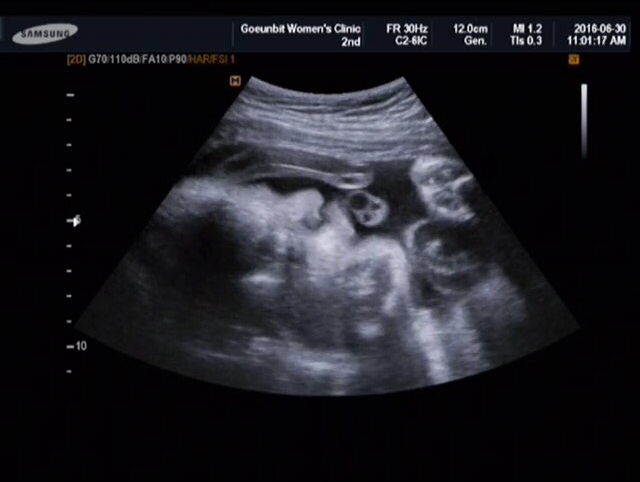

임신 33주

3주 전 아기의 체중은 정확히 1.19키로였다. 선생님께서 주수에 비해 아기가 작다고 하셔서 일부러 그 주에 수박이랑 과일을 많이 먹어주었는데 다행히 아기는 3주 만에 800g이 늘어났다. 이제 2키로대로 진입! (내가 살찌는 건 싫지만 아기가 찌는 건 너무 기분 좋은 현상이야) 선생님 말씀으로는 아기가 이제 자리를 잡았다고 했다. 다행히 역아도 아니고 양수도 넉넉해서 태동도 잘한다고 하셨고 말이다. 3주 만에 800g이 늘어난 만큼 아이의 얼굴에도 살이 조금 붙었는데 저번보다 아이는 얼굴을 잘 보여주지않았다. (늘 네 얼굴 보러 가는 낙으로 갔는데 )그런데 그것도 그럴 것이 이제 주수가 점점 늘어가면 갈수록 선생님께선 아기 얼굴 보기가 더 힘들어질 거라는 말씀을 하신다. 그렇다면 이제 출산할 때까지 오매불망 기다려야 될 것 같다. 그리고 36주 뒤부터는 이제 일주일에 한 번씩 정기검진이 있다고 하셨다. 하...정말 얼마 남지 않았다는 생각을 하니 기분이 묘해졌다.